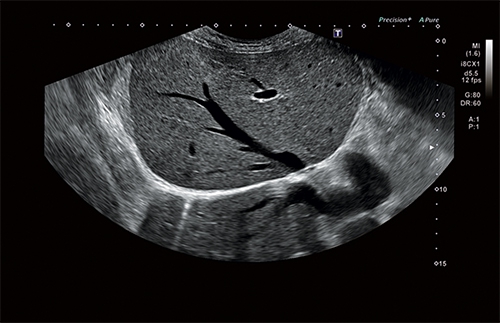

4D

Объемное сканирование в реальном времени больше не фантастика, а впечатляющее достижение современных технологий. С помощью сканирования этого типа вы сможете рассмотреть даже самые мелкие детали изображения под любым требуемым для проведения исследования углом.

• Программно-технологический комплект 4D: рендеринг поверхности, визуализация полостей, мультипланарная реконструкция, MultiView для ультразвуковой томографии и ряд других функций